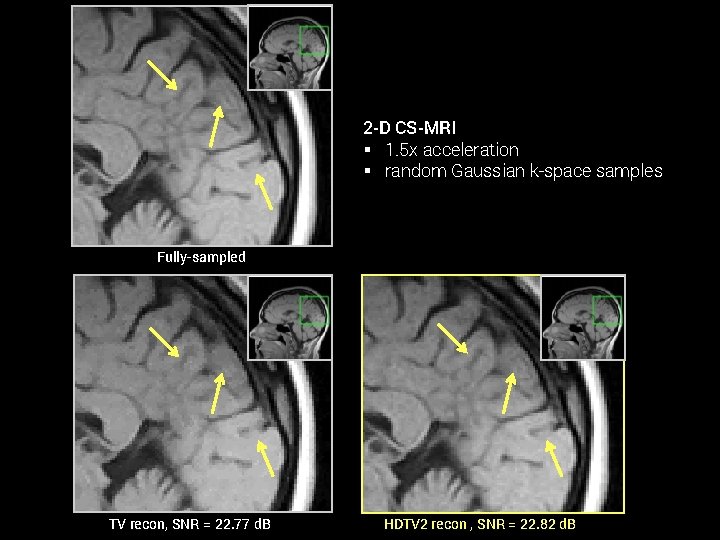

Comparison of HDTV and TV in 2 -D § HDTV routinely outperforms TV for many image recovery problems § Modest increases in computation time (~2 -4 fold) 2 -D TV Comparison. SNR (in d. B) of recovered images with optimal reg. param. (Hu et al, 2014) Denoising Lena Brain Deblurring Cell 1 Cell 2 CS-MRI Brain Wrist TV 27. 35 27. 60 15. 66 16. 67 22. 77 20. 96 HDTV 2 27. 65 28. 05 16. 19 17. 21 22. 82 21. 20 HDTV 3 27. 45 28. 30 16. 17 17. 20 22. 53 21. 02 SNR vs. CPU time of HDTV and TV. (Hu, Y. , & Jacob, M. , 2012) CS-MRI, 2 x accel. CS-MRI, 4 x accel. Denoising, SNR=15 d. B

2 -D CS-MRI § 1. 5 x acceleration § random Gaussian k-space samples Fully-sampled TV recon, SNR = 22. 77 d. B HDTV 2 recon , SNR = 22. 82 d. B